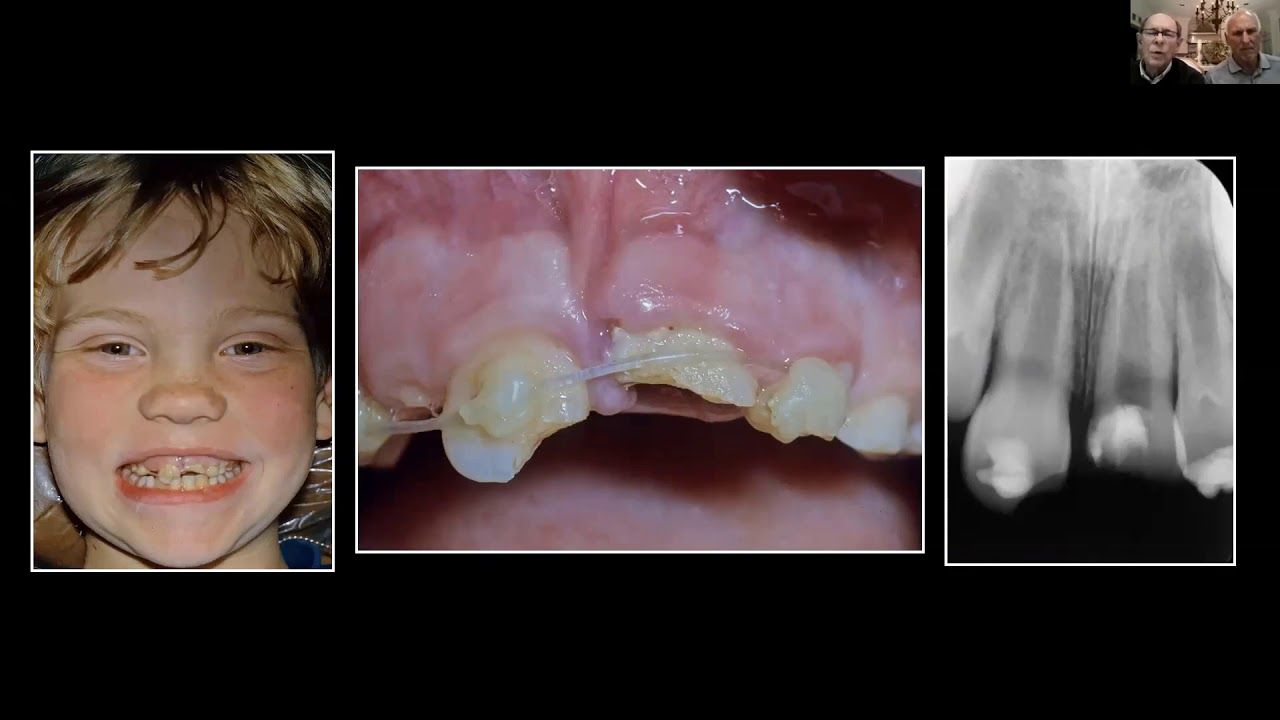

Steiner Mathews ridge preservation

How do we preservie a ridge in childhood trauma? The strategies that you are about to see are unique in dentistry, far more predictable in outcome. Watch as you see how conservative management of the trauma patient creates outstanding ridge preservation for a lifetime.